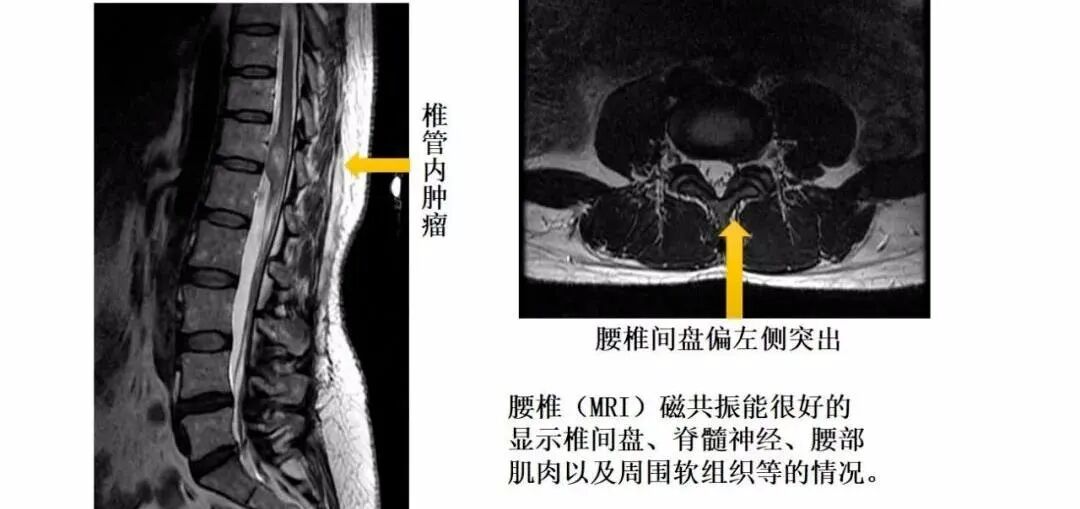

三、核磁共振(MRI):这是一种利用强磁场和射频信号的高级检查方法。

拍胃肠机怎么收费【医学影像科普】腰疼想拍片检查,您拍对了吗?_https://www.jmylbn.com_新闻资讯_第10张

拍胃肠机怎么收费【医学影像科普】腰疼想拍片检查,您拍对了吗?_https://www.jmylbn.com_新闻资讯_第11张

拍胃肠机怎么收费【医学影像科普】腰疼想拍片检查,您拍对了吗?_https://www.jmylbn.com_新闻资讯_第12张

优点:磁共振检查在软组织成像上更胜于腰椎CT。可以很好地观察腰椎间盘的情况,更清晰地显示椎间盘的形态及其与硬膜囊、神经根等周围组织的关系。在脊髓病变、炎性病变、出血性病变及腰部肌肉病变等方面也具有优势。此外,磁共振检查不存在X线辐射,是较为安全可靠的检查。

缺点:价格较高,时间较长,有明确的限制人群,如有金属植入物、胰岛素泵或者心脏起搏器的患者。此外,因磁共振机器的孔径一般都不是很大,所以患有幽闭恐惧症的患者,也不建议首选腰椎MRI。